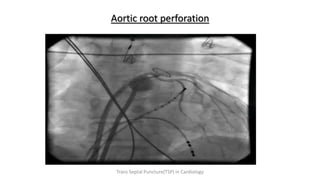

AORTIC ROOT STAIN

• Abandon procedure

• Observe for

hemodynamics/effusion

• Only a needle puncture -

wait and watch.

• defer the procedure and

repeat echo in regular

intervals

Aortic root perforation

AORTIC ROOT STAIN •Abandon procedure • Observe for hemodynamics/effusion • Only a needle puncture - wait and watch. • defer the procedure and repeat echo in regular intervals Trans Septal Puncture(TSP) in Cardiology

• 82.

Aortic root perforation TransSeptal Puncture(TSP) in Cardiology